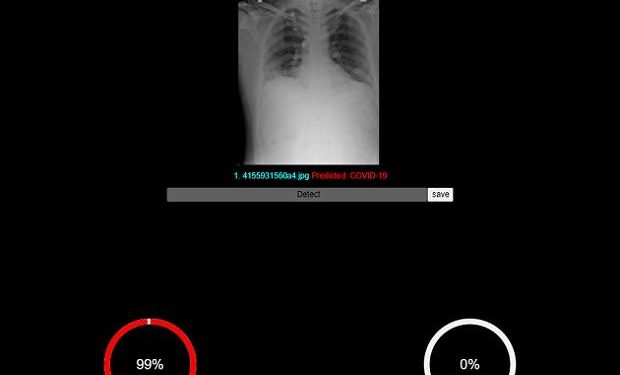

The AI feature with existing models have improved the accuracy of the software. Being a machine learning tool, the accuracy will improve continually. Chest X-rays of RT-PCR (reverse transcription polymerase chain reaction) positive hospitalized patients in various stages of disease involvement were retrospectively analyzed using AI (deep learning and convolutional neural network) models by an indigenously developed deep learning application by CAIR-DRDO for Covid-19 screening using digital chest X-rays. The companies said the algorithm showed an accuracy of 96.73 per cent.